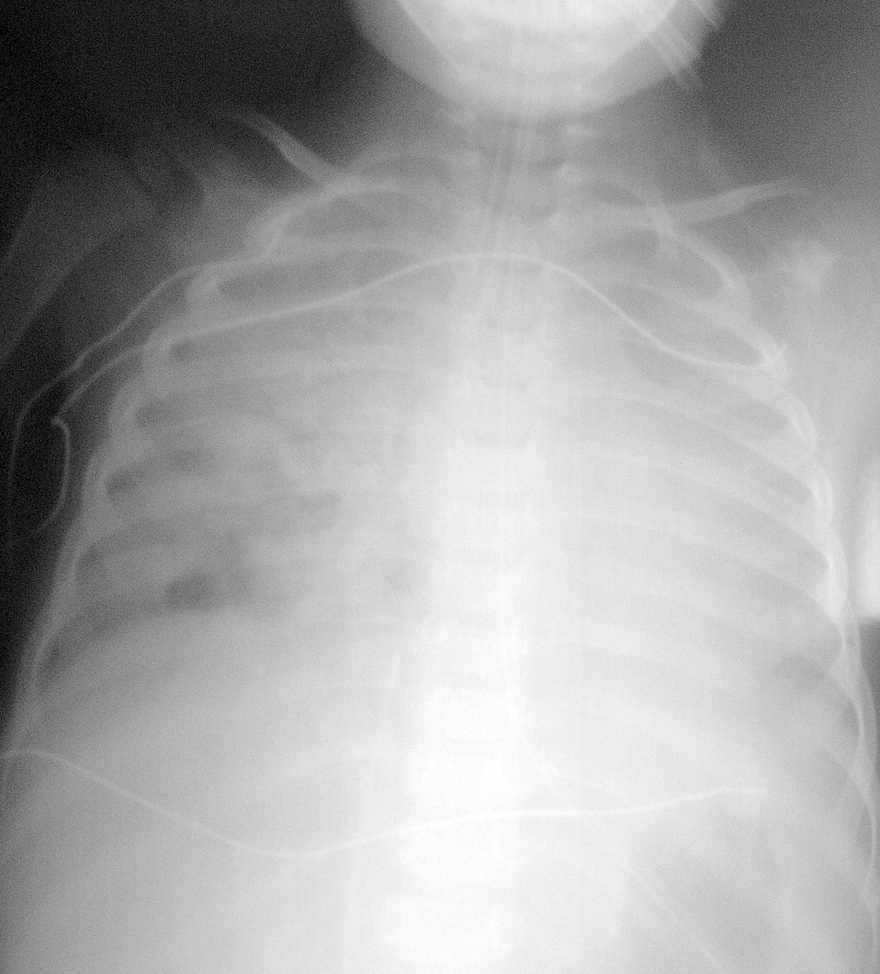

El paciente presentaba una coagulopatía que requirió tratamiento con plasma fresco congelado y vitamina K, así como anemia de 8 g/dl de hemoglobina (Hg) que requirió transfusión de concentrados de hematíes. La función respiratoria fue empeorando progresivamente, presentando presiones altas en la vía aérea (pico de 45-50 cm H2O, meseta de 19 cm H2O, compliance dinámica de 3,4 ml/cm de H2O y estática de 12 ml/cm H2O). Se asoció NO2 hasta 30 ppm al tratamiento. Tras aumentar progresivamente la presión positiva al final de la espiración (PEEP) hasta 7 cm H2O, el pulmón derecho aparecía más aireado, y tras la resolución del componente atelectásico que estaba asociado a la neumonía (fig. 1) se apreciaron dos imágenes compatibles con abscesos o bullas en el pulmón derecho (fig. 2). La evolución posterior fue hacia un síndrome de distrés respiratorio agudo (fig. 3). Se inició tratamiento con ventilación de alta frecuencia con una mejoría inicial de la oxigenación que no se mantuvo posteriormente.

Figura 2. Abscesos o bullas en el pulmón derecho.